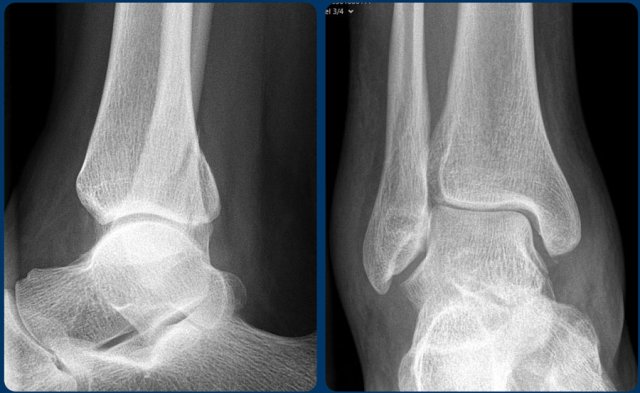

First Question: Is it a Weber A, B or could it be a Weber C? Then try to figure out the stage and determine whether the ankle is stable or unstable.

You can look at the next images for a discussion of the images.

Scroll through the images.

It is a stage 4 Weber B fracture, which is unstable.